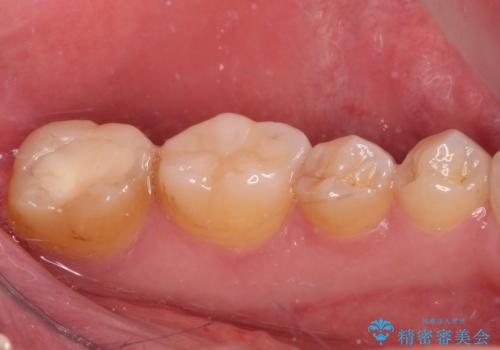

長期海外赴任が近いとのことで、出発に間に合うようにアポイントを調整して治療を進めて行きました。

中途半端に歯冠の見えている親知らずもあったため、そちらも出発前に抜歯を行いました。